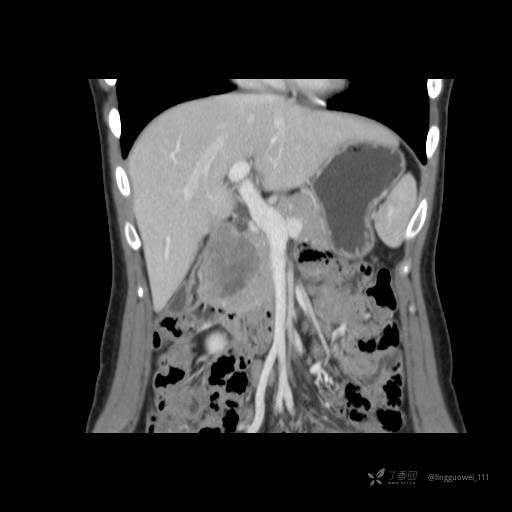

患者性别:女

患者年龄:28岁

主诉:体检发现胰腺病变,行 CT检查。

平扫:

动脉期:

门脉期:

延迟期: